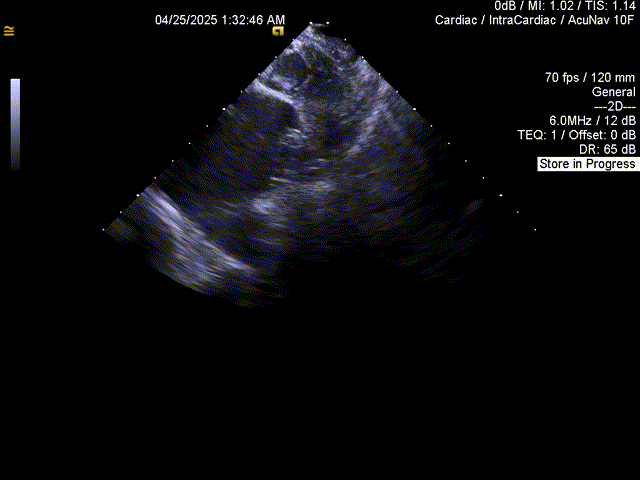

术前经食道超声心动图检查:双房及双心耳内未见血栓,评估左心耳形态及大小

ICE下评估PASS原则

封堵器位置及压缩比良好,多普勒检查无残余分流

超声确认

封堵器位置良好,术后无心包积液